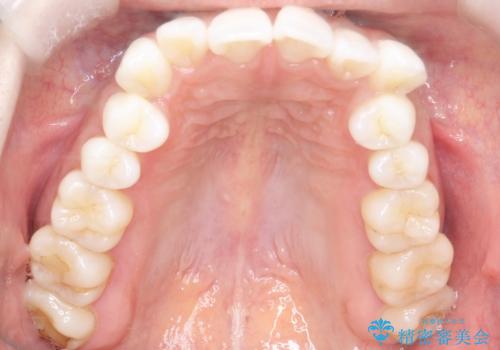

歯並びと横顔のバランスを整えるためには、前歯を後方に移動させるスペースの確保が必要です。そのため、上下左右の第一小臼歯(合計4本)を抜歯し、ワイヤー矯正で前歯の突出感と叢生(がたつき)を同時に改善する治療計画を立てました。歯を抜くことに抵抗がある方も多いですが、口元の印象を変えるためには非常に効果的な方法です。

上下左右の小臼歯を抜歯後、ワイヤー矯正装置を装着し、全体のバランスを見ながら歯を移動させていきました。特に前歯の後方移動では、抜歯スペースを活かして口元を内側に下げることに重点を置きました。また、八重歯も時間をかけて丁寧に整列させ、左右の正中(真ん中の位置)もぴったりと揃えることができました。